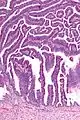

The name of the lesion describes it microscopic appearance. It has nipple-like structures with fibrovascular cores (papillae) that are long in relation to their width (villus-like), which are covered with a glandular pseudostratified columnar epithelium.

Intermed. mag.